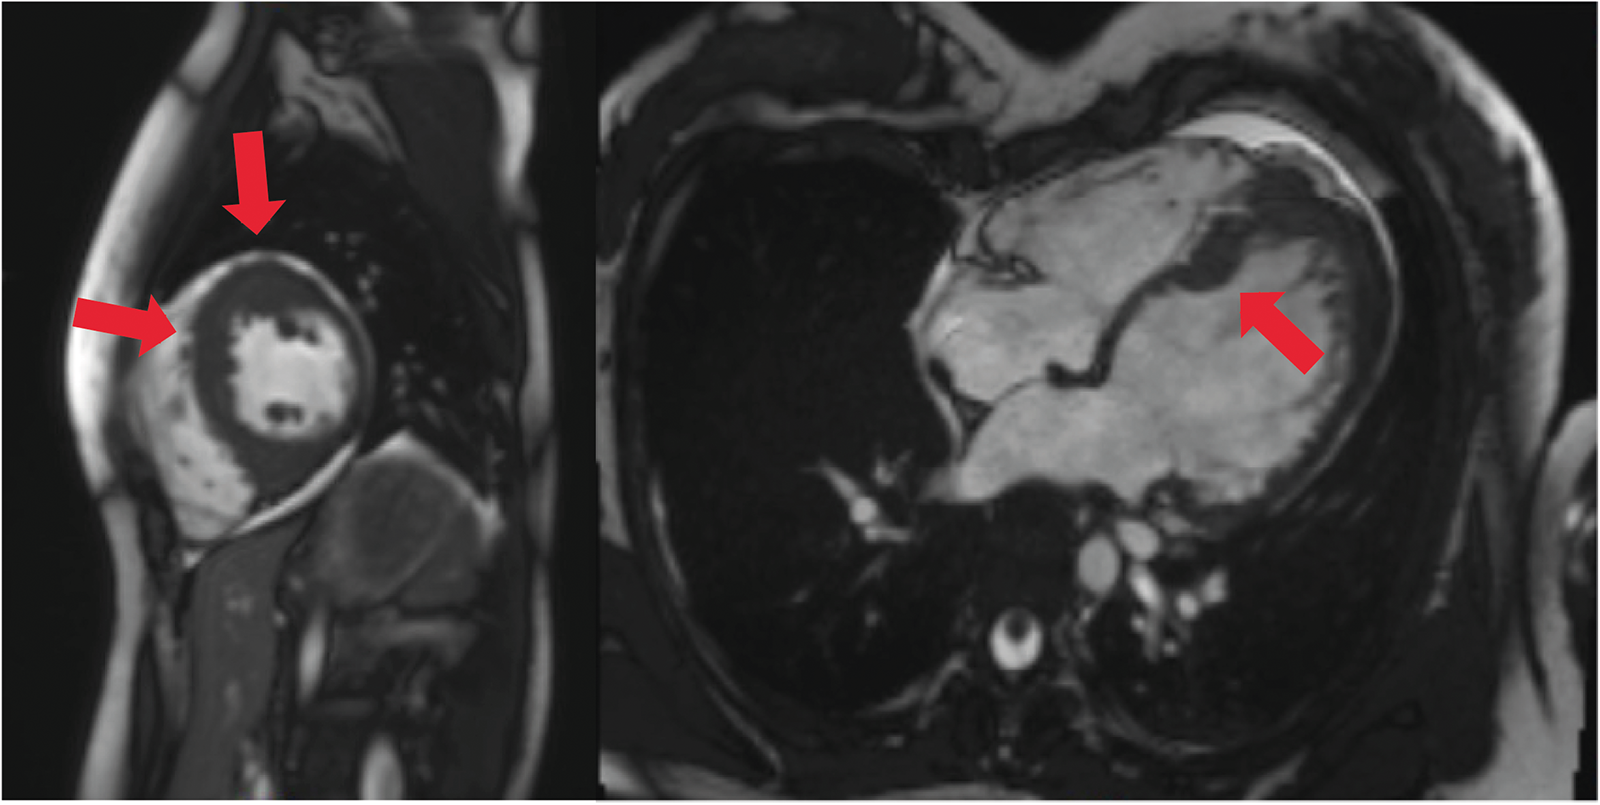

An 18-year-old woman survived an exercise-related SCA due to VF and immediate cardiopulmonary resuscitation. Initially, an underlying myocarditis was suspected. No indication of heart insufficiency had been detected. The patient has negated other symptoms such as angina pectoris, dyspnea, or previous arrhythmic events, like palpitations or syncopes, before the first hospitalization (Table 1). However, cardiac magnetic resonance imaging was not diagnostic but showed pathologic LV thickening of the anteroseptal and mid-anteroseptal and apical parts (Figure 1, up to 21 mm), leading to the diagnosis of non-obstructive HCM. MRI functional parameters were nearly normal [ejection fraction 53.5%, end-diastolic volume (EDV) 79.1 ml/m2, end-systolic volume (ESV) 36.8 ml/m2, ejection volume 42.4 ml/m2, heart-minute volume 4.9 L/min, LV mass 83.3 g/m2]. In addition to the diagnosed non-obstructive HCM with pathologic LV thickening of the anterior, middle, and anterior-septal and apical parts until up to 21 mm, an obstruction in the LV outflow tract (LVOT) could not be confirmed. Gadolinium application showed myocardial late enhancement and fibrosis, particularly in the hypertrophied LV sections. Ajmaline testing was negative for Brugada syndrome. Initially, a subcutaneous ICD (S-ICD) was implanted. Striking was a post-shock pacing with 22 pulses of 26 s duration. We interpret this as a depression of the sinus node due to the 65-J shock. A medication consisting of 1.25 mg/day bisoprolol and 1.25 mg/day ramipril was initiated upon discharge. The baseline ECGs showed a normal but bradycardic sinus rhythm (45 bpm; Figure 2A) and conduction at rest without any disturbances of repolarization or LV hypertrophy.

Figure 1. Cardiac MRI, four-chamber view. Depicted long- and short-axis cine images. Red arrows: thickened LV septal and apical wall (up to 20 mm); small apical pericardial effusion.